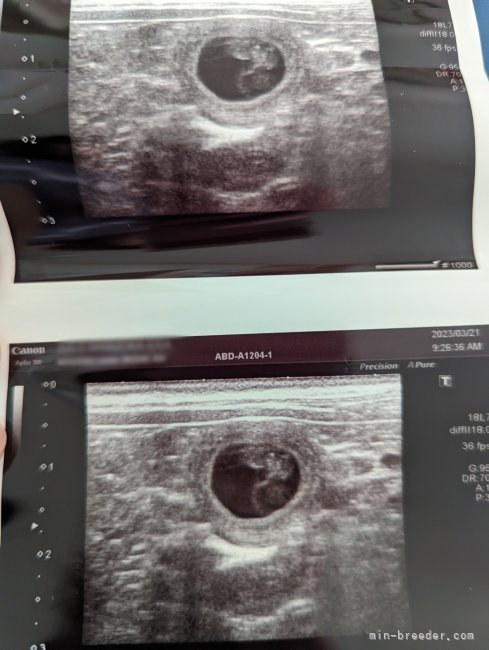

ミニチュアシュナウザー🐾出産予定4月下旬にミニチュアシュナウザー出産予定です🐣 断尾はしない予定ですので、尻尾の長いナチュラル...